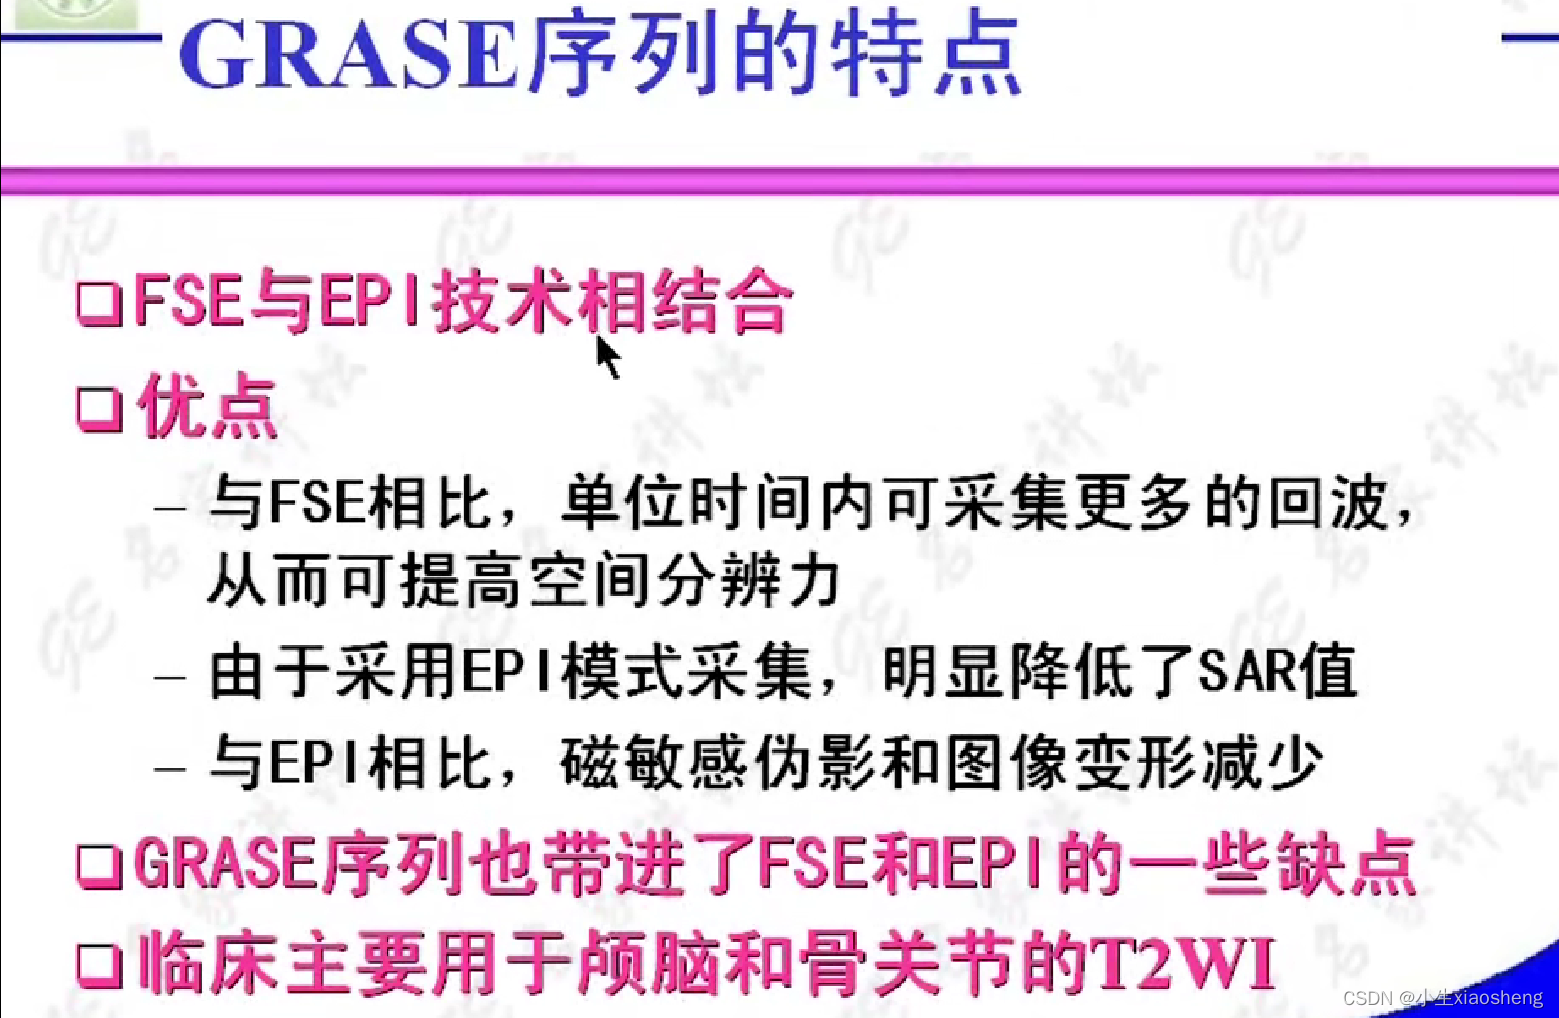

八、PRESTO和GRASE序列